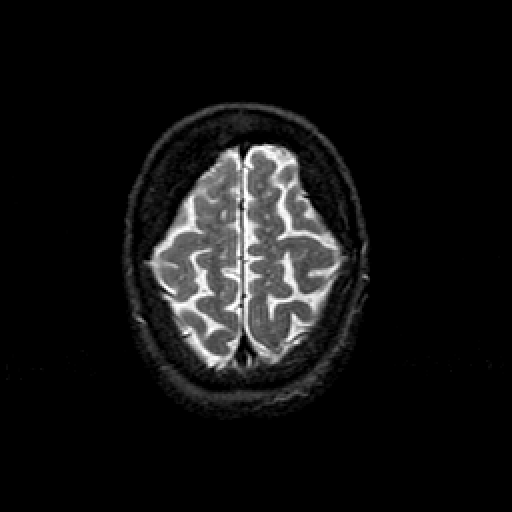

T2-weighted structural MR: Slice 45

Slice 45